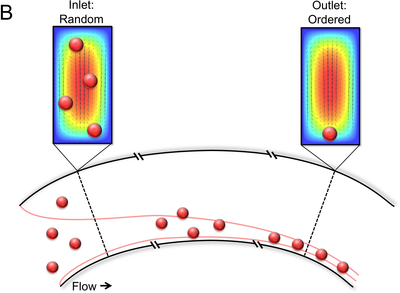

在许多医疗操作和测试中,分离出我们关注的细胞做进一步分析是非常必要的。微流控彻底改变了进行这些测试的方式,比如能够通过血样检测癌症。 在最有前景的分离并浓缩细胞的微流控技术中,有一种称为惯性聚焦的技术 ...扩展阅读